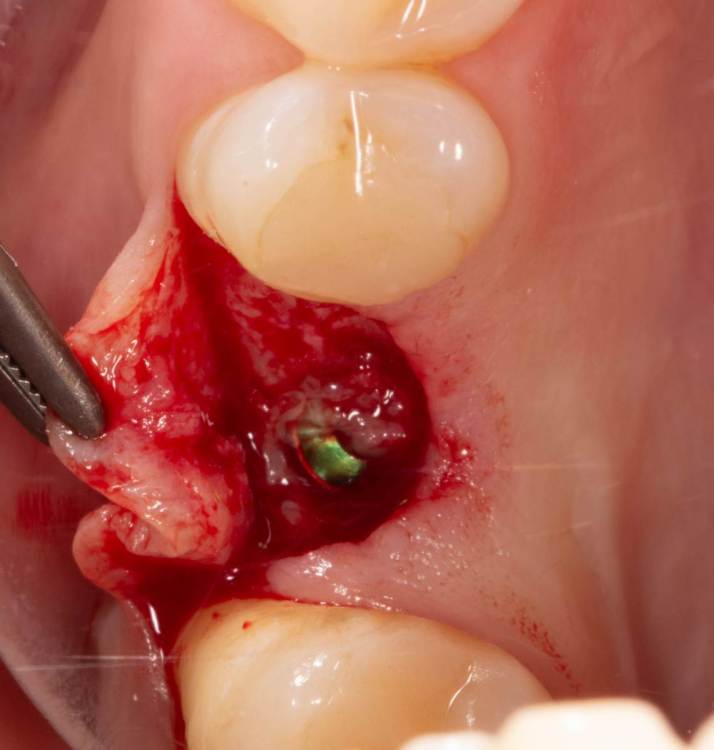

Женька Опубликовано 14 ноября, 2021 Автор Поделиться Опубликовано 14 ноября, 2021 Какой-то чудной зсл у меня получился... но это от недостатка опыта 100%. В общем фото сделал всего 2шт , скину в понедельник. Итак про ЗСЛ. Мой протокол: разрез, скелетирование, подшиваю лоскут для лучшей визуализации, далее пилотное дентиум не доходя 1-1.5мм, далее расширяю отверстие до нужного размера (здесь 3.8 имплантиум) и потом беру остеотом того же размера и стучим до появления "тупого" звука или ощущения "проваливания". Остеотомы у меня китайские, но со стоперами. Начинаю стучать и почти сразу чувствую, что провалился. Зондирую "зонтиком" - никакой эластичной подвижности... стучу ещё, тоже самое. Заметил, что стопер упирается проксимально в 2.7. Выкручиваю стоперы совсем. Стучу, звук особенно не меняется, но пациент отмечает неприятные ощущения. По остеотому 8мм (нативной кости 7 с копейками). Снова зондирую, снова не чувствую мембраны , пациент же говорит, что что-то есть, двигается будто. Решив, что хватит мучать бедолагу нарезаю пару столбиков Белкозина и пакую с помощью остеотома. Инсталирую имплантат и пациент отмечает чрезмерное распирание и легкую болезненность (еще 1.5 мм имплантата не погружено). Продолжаю глубить, всё спокойно. В итоге остановился на 1.5мм заглублении и заглушке, не рискнул ставить фдм, торк около 10). Вырезал сст, подшил вестибулярно и наконец-то закончил. Судя по РГ я подломил не только кортикальную пластинку, но и приличный кусок губки? Критично ли? После отметил лёгкую заложенность носа, без геморрагий. 4 Ссылка на комментарий

Женька Опубликовано 15 ноября, 2021 Автор Поделиться Опубликовано 15 ноября, 2021 Как и обещал... всего два фото... Когда-нибудь я буду всё успевать и делать нормальный интраоперационный фотопротокол) Ссылка на комментарий